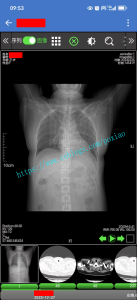

2021年4月偶然的机会接触到一家做SaaS的云HIS公司,需要做基于SaaS纯WEB版本的云PACS系统。出于对个人技术的积累和挑战离开了一起奋斗10年的HF,跳槽到做HIS互联网医疗的SaaS公司。经过一年左右的开发和集成终于在2022年5月开始实施上线第一家全院级PACS,完成基于SaaS的纯BS架构的云PACS系统。到目前为止已经经历过三级医院和区域医共体的考验。

简单的描述下系统的特点:后端基于SpringBoot开发,Dicom基于dcm4che实现C-STORE、C-FIND、C-MOVE、Worklist等通信协议并集成于SpringBoot项目上。Dicom-Viewer部位为纯JS实现dicom原文件的解析和渲染。RIS登记、报告等工作流程基于Vue开发。支持DirectShow协议的采集卡或显微镜头,支持纯WEB模式进行采集超声、内镜、病理等类型图像。

1.支持电脑、手机、平板等设备,支持HarmonyOS、IOS、android、window、linux、信创、麒麟等主流操作系统,支持电子胶片,可在任意终端任意系统的H5浏览器上调阅医学影像。